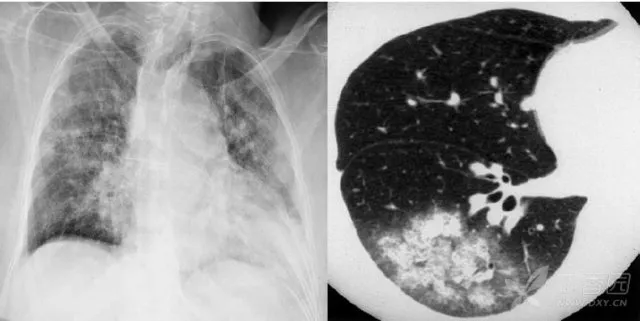

大葉性肺炎胸部影像

簡單來講,肺炎出現(xiàn)較大的病灶,局限在一個肺葉,就叫大葉性肺炎。大葉性肺炎也叫肺泡性肺炎,這是因為大葉性肺炎的炎性滲出主要發(fā)生在肺泡。細(xì)菌、病毒、真菌、以及肺炎支原體等非典型病原體都可以引起大葉性肺炎。